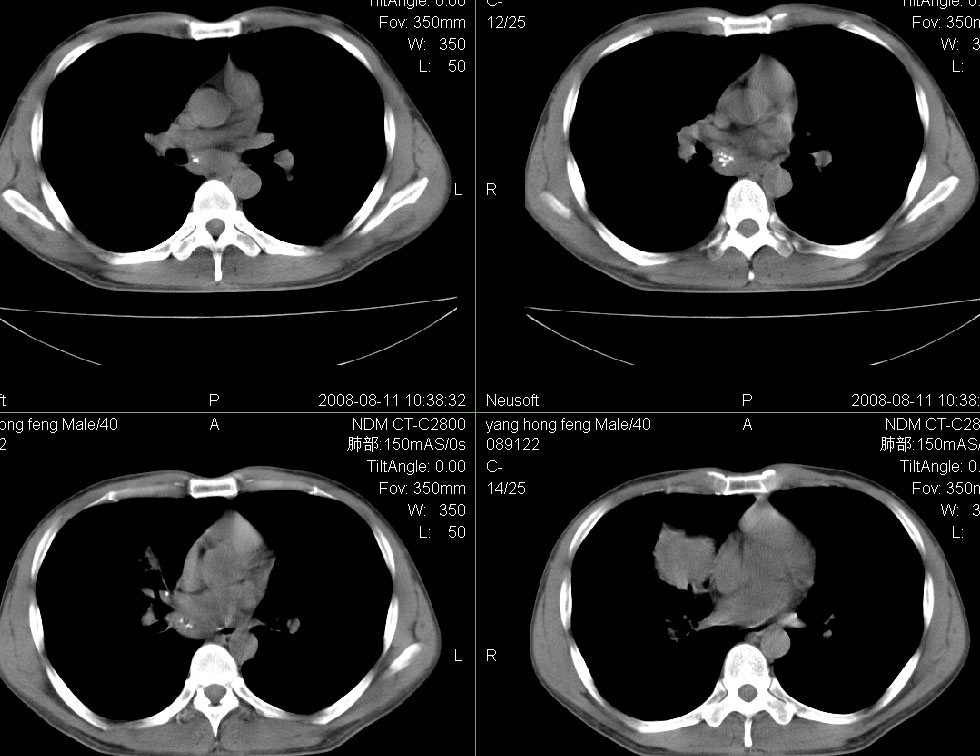

标题: CT15138:男,40,咳嗽胸痛. [打印本页]

标题: CT15138:男,40,咳嗽胸痛.

外院穿刺未见癌细泡,结核菌素实验阳性,未正规治疗2个月复查病灶及纵隔淋巴结增大

结合病史及临床表现考虑右侧中心型肺癌纵隔转移,

右侧中心型肺癌纵隔转移!

右肺中叶肺癌,纵隔淋巴结转移.

考虑   右肺中叶肺癌,纵隔淋巴结转移.建议穿刺活检。炎性假瘤待排

考虑右肺中叶周围型肺癌并纵隔淋巴结转移。